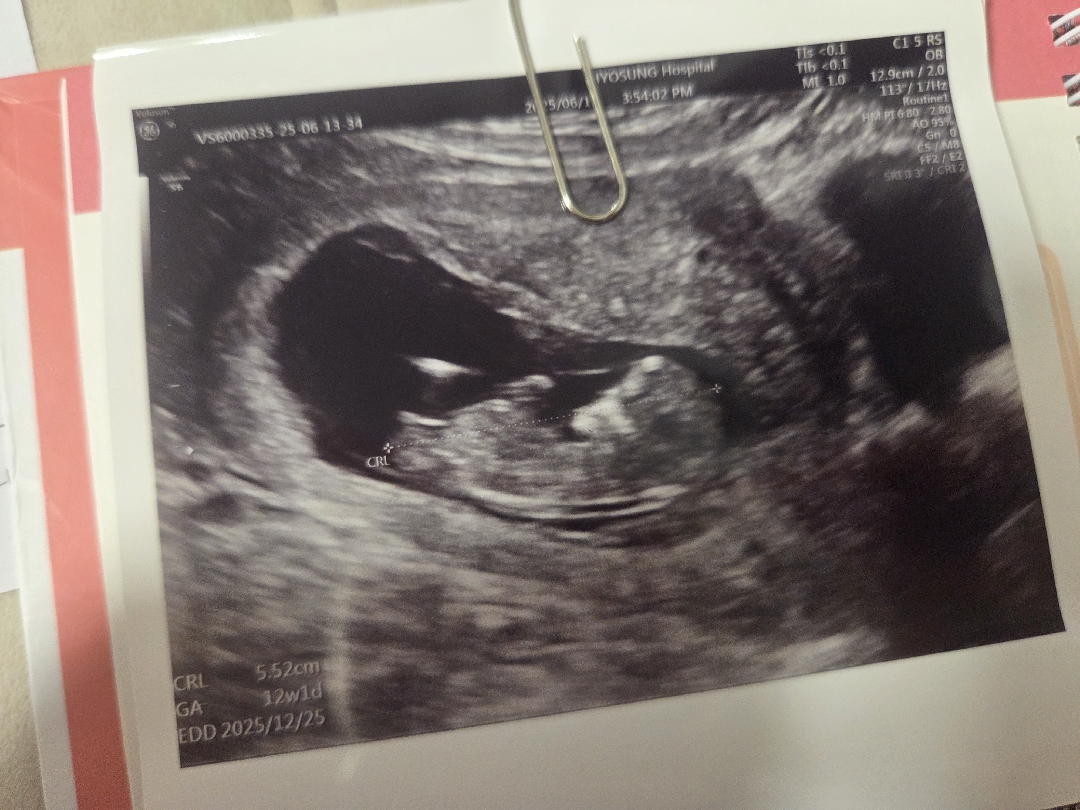

12주차 각도법 봐주실분!

동영상 캡처로 올렸는데 저도 긴가민가해서요ㅠㅠ

딸 느낌이에요!

그런가요? 카페에서도 그렇다 하시던데 너무 길쭉해서 반전될 수 도 있다네요ㅎㅎ 16주 되야 정확하겠어요ㅠ